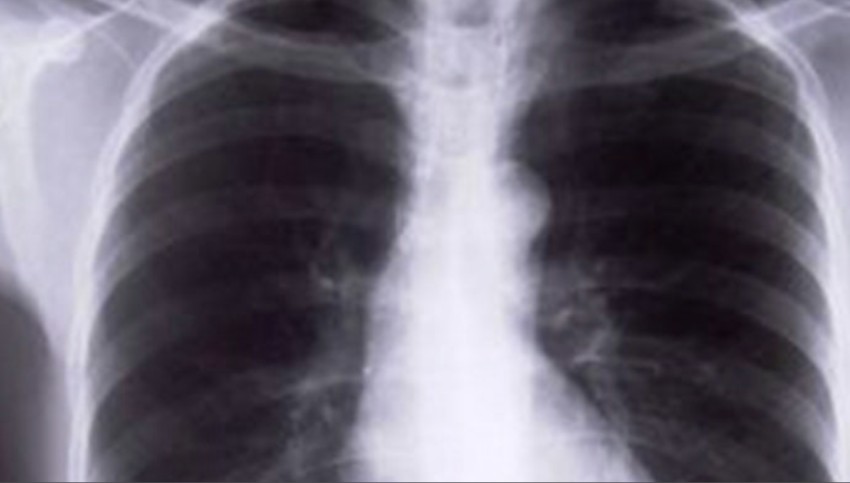

Veracruz se mantiene en el primer lugar nacional en número de casos de tuberculosis respiratoria.

La Secretaría de Salud del Gobierno Federal dio a conocer en su reporte epidemiológico que al corte de la semana número 14, la entidad veracruzana registró 526 casos de dicha enfermedad.

En el segundo lugar se ubica Baja California; y en tercero, el estado de Nuevo León.

En el caso de Veracruz, 328 casos corresponden a hombres, y 198, a mujeres.

La cifra de las primeras 14 semanas del año es ligeramente inferior a la registrada en el mismo periodo de 2023, cuando se reportaron 555 casos.